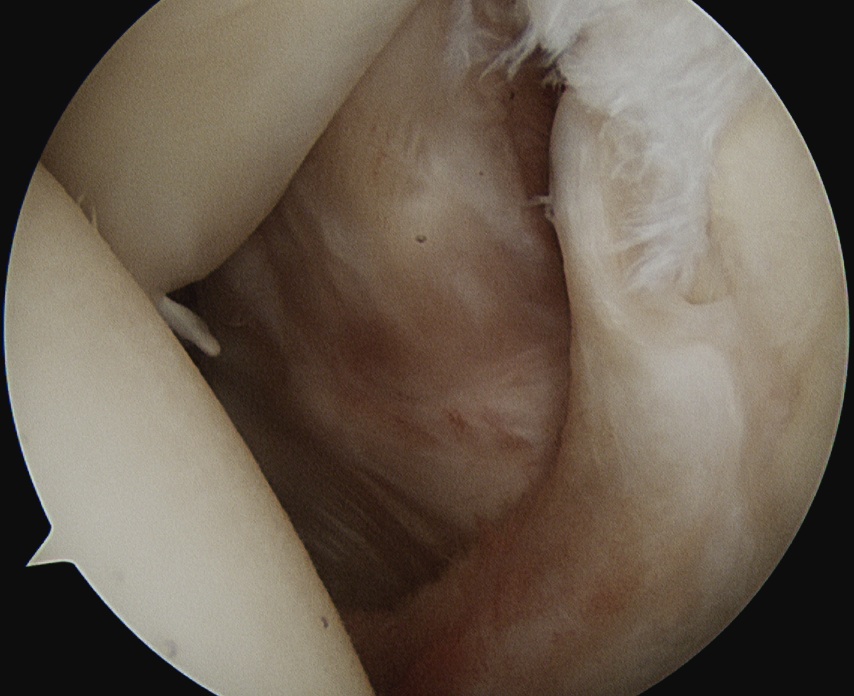

Subacromial space

- total bursectomy plus acromioplasty

- use tagging sutures to identify SSC

Prepare footprint

- debride